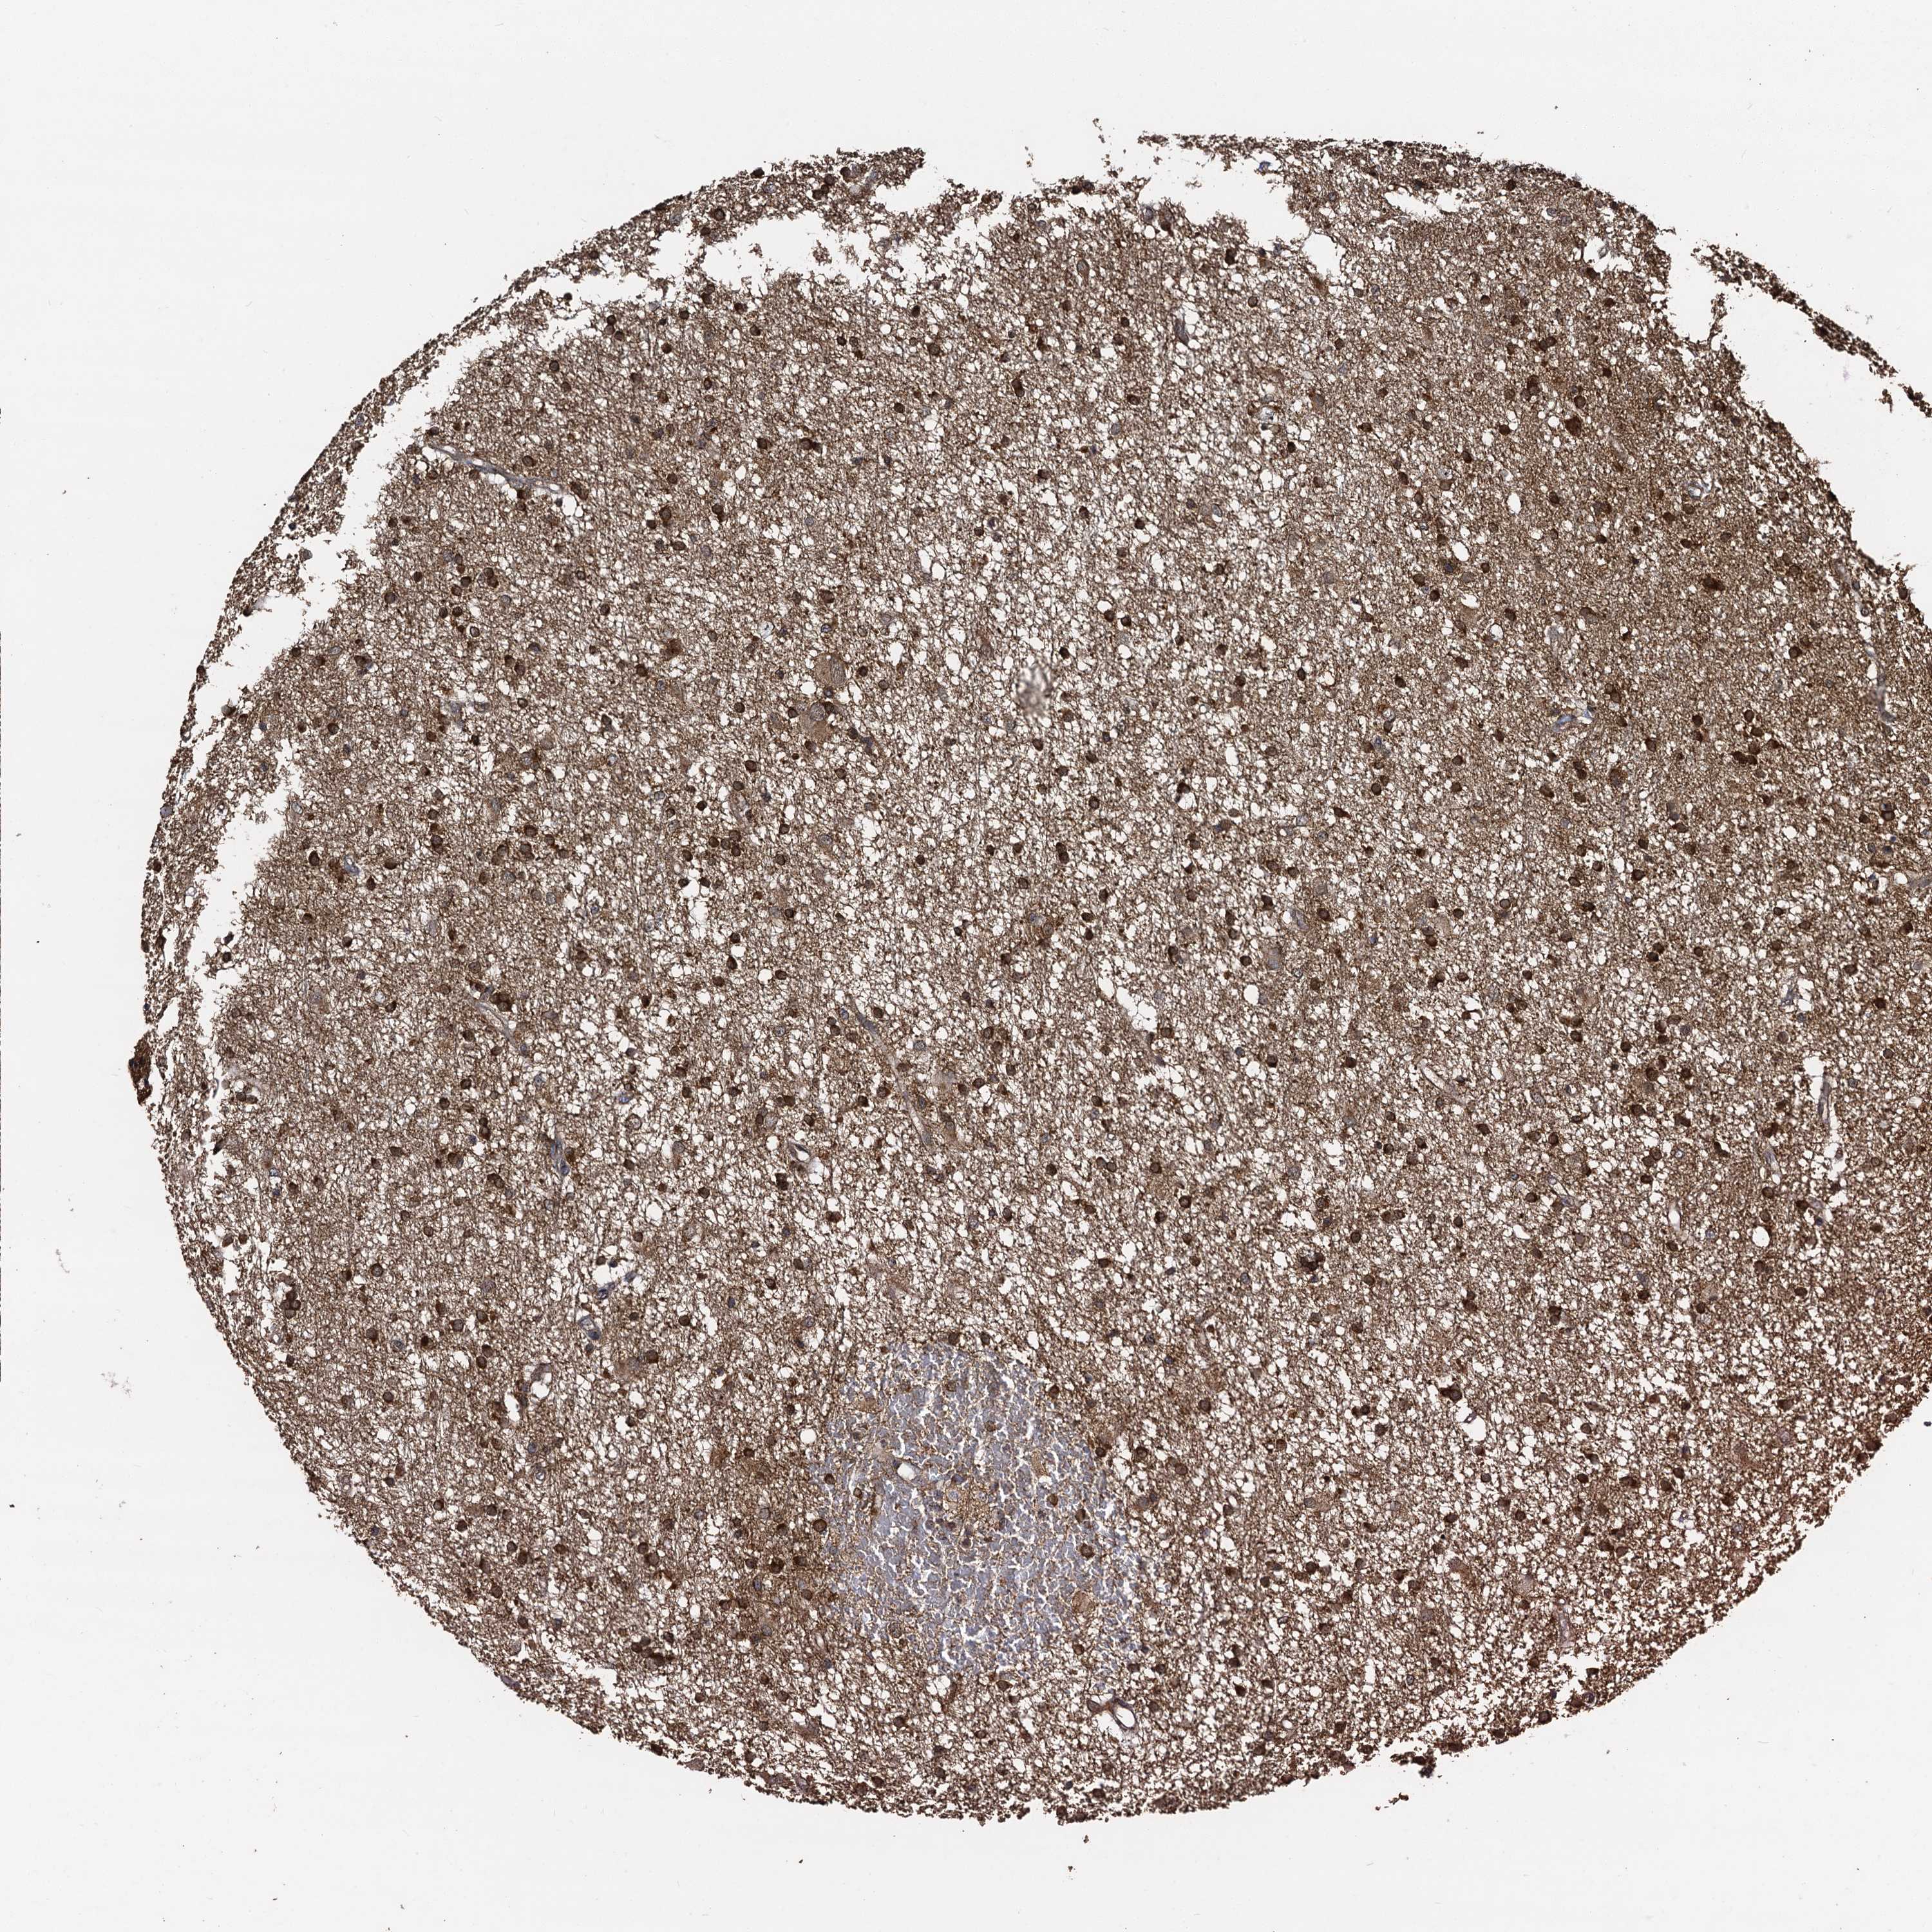

GLIOMA - Protein expressioni

A mouse-over function shows sample information and annotation data. Click on an image to view it in a full screen mode. Samples can be filtered based on level of antibody staining by selecting one or several of the following categories: high, medium, low and not detected. The assay and annotation is described here.

Note that samples used for immunohistochemistry by the Human Protein Atlas do not correspond to samples in the TCGA dataset.

Antibody stainingi

Antibody staining in the annotated cell types in the current human tissue is reported as not detected, low, medium, or high, based on conventional immunohistochemistry profiling in selected tissues. This score is based on the combination of the staining intensity and fraction of stained cells.

Each image is clickable and will lead to virtual microscopy that enables deeper exploration of all samples and also displays staining intensity scores, fraction scores and subcellular localization as well as patient and tissue information for each sample.

Antibody HPA041507

Antibody HPA041599

Staining

High

Medium

Low

Not detected

Intensity

Strong

Moderate

Weak

Negative

Quantity

>75%

75%-25%

<25%

None

Location

Nuclear

Cytoplasmic/membranous

Cytoplasmic/membranous,nuclear

Glioma, malignant, High grade

Glioma, malignant, Low grade